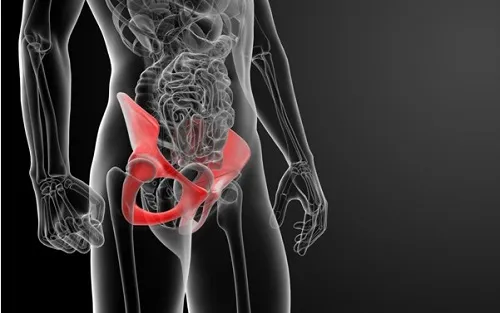

고관절은 골반의 관골구와 대퇴골두를 연결하는 관절입니다. 골반과 다리가 만나는 지점에 위치하며 체중을 지탱하고 다리의 움직임을 가능하게 합니다.

또한 "엉덩이 관절"이라고도 불리는 이 관절은 뼈와 뼈가 연결되어 자유로운 움직임을 가능하게 하는 신체 부위로, 허벅지와 종아리를 포함한 다리 전체를 움직일 수 있도록 돕습니다. 고관절의 움직임과 기능은 걷기, 달리기, 앉기 등과 밀접하게 연관되어 우리 몸의 움직임과 일상 활동에 핵심적인 역할을 수행합니다.